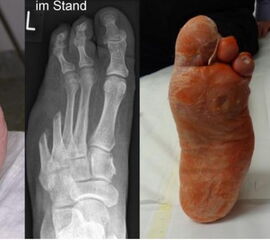

- Operative Behandlung von Druckstellen durch Hallux valgus

Aufgrund einer Fehlstellung der Großzehe nach außen (Hallux valgus) kann es zu Druckstellen bzw. Hautläsionen zwischen der 1. und 2. Zehe sowie kommen. Gefährdet ist auch die Haut auf der Innenseite des Fußes über dem Großzehengrundgelenk. Sollten hier konservative Therapiemaßnahmen (Polsterung/Schuhzurichtung) versagen, ist eine operative Korrektur des Hallux valgus anzuraten. - Operative Behandlung von Druckstellen durch Hammerzehen

Zum Lesen der Bildbeschreibung und Vollansicht bitte Bild anklicken. Fotos: Alexander Mehlhorn

- Operative Behandlung von Druckstellen durch Überlänge eines oder mehrerer Mittelfußknochen

Anlagebedingt oder nach Amputationen kann es zu einer Überlänge von einem Mittelfußknochen relativ zu den anderen Mittelfußknochen kommen. Dies führt zu einer erhöhten Druckbelastung an der Fußsohle. Zunächst treten Schwielen auf, im Verlauf kommt es dann zu offenen Stellen und einem Ulkus. Sollten hier konservative Therapiemaßnahmen (Polsterung/Schuhzurichtung) versagen, ist eine operative Verkürzung oder Anhebung des entsprechenden Mittelfußknochens sinnvoll, um den Druck zu reduzieren. Auch dies ist heute meist minimalinvasiv in Schlüssellochtechnik möglich.